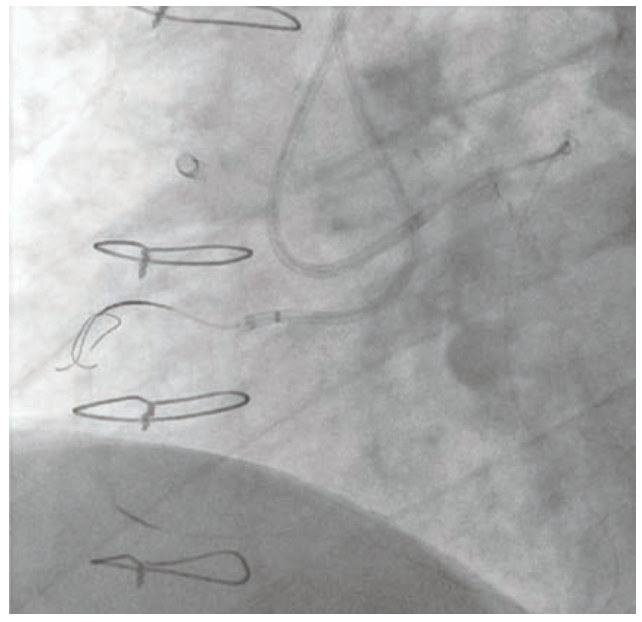

Dual access was achieved with a 7 French Amplatz Left (AL)-1 guide catheter and a 7 French Extra Backup (EBU) 3.75 guide catheter. Based on dual-injection angiography, the proximal cap was ambiguous due to a tortuous right ventricular (RV) marginal branch and the occlusion was long (>20 mm) (Figure 1). Therefore, we decided to attempt retrograde techniques first. After administering heparin to a goal activated clotting time (ACT) of >350, a workhorse wire was advanced through a low-profile microcatheter into the first septal perforator. The wire was exchanged for a specialty wire that was used to cross septal collaterals. We had difficulty advancing the microcatheter into the septal perforator, as it was jailed with a previously placed stent (Figure 2). Here, we used a 1.5 mm x 20 mm TAKERU balloon to dilate the stent struts. We were able to advance the microcatheter into the septal perforator and into the distal vessel (Figure 3). The connection was made with a reverse controlled antegrade and retrograde tracking (R-CART) technique (Figure 4). Overlapping drug-eluting stents were placed and aggressively post dilated. Final angiography demonstrated no residual stenosis, dissection, or perforation (Figure 5). The patient was placed on dual antiplatelet therapy for six months.